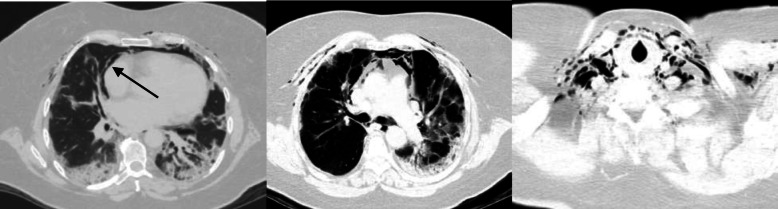

Fig. 2.

Computed tomography of the chest without contrast of Patient 1. There is a pneumopericardium (left) and extensive pneumomediastinum (middle) extending along soft tissues of the anterior and lateral chest wall as well as anterior neck soft tissues (right)